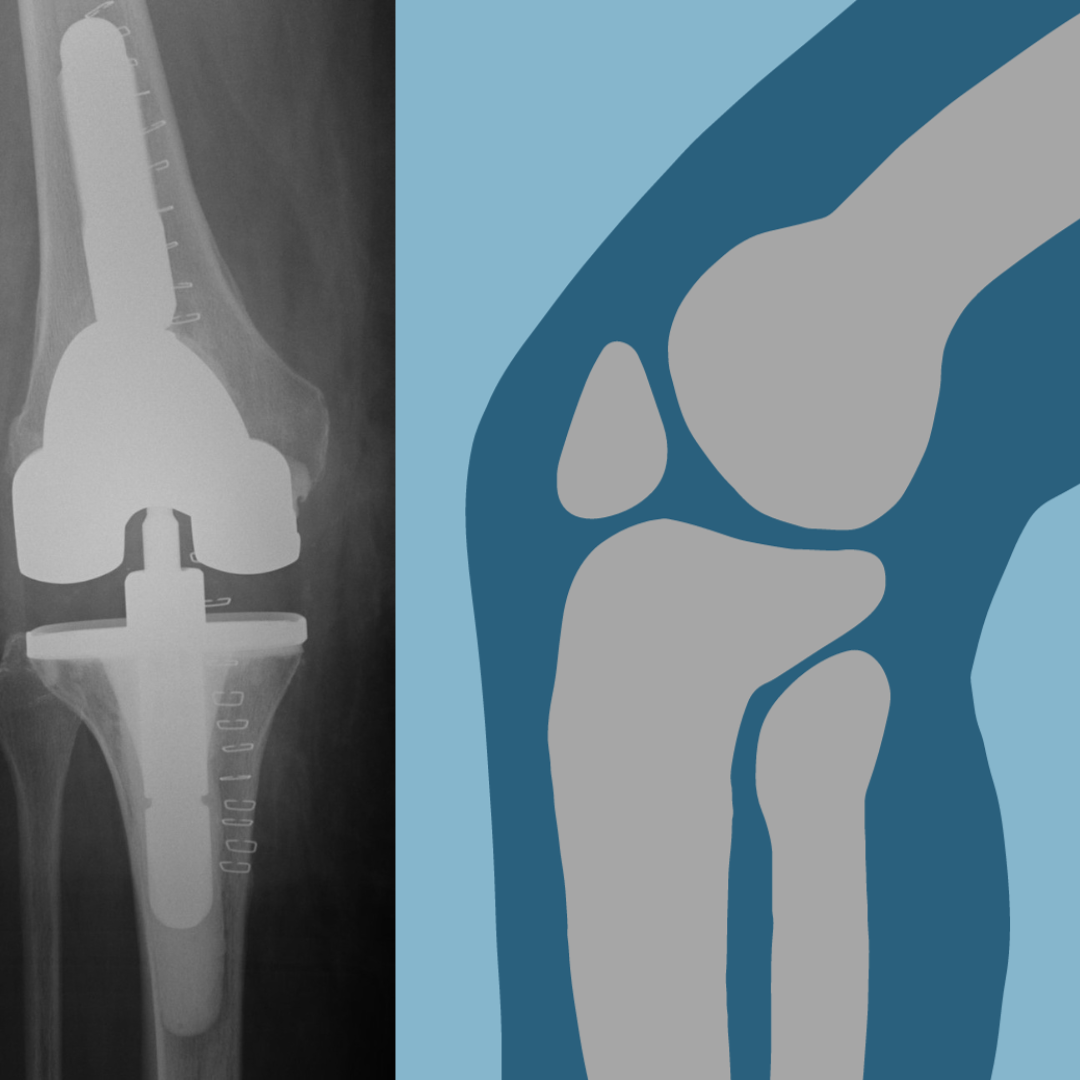

Early mobilisation; initiating physical activity soon after total knee replacement (TKR) surgery, has gained widespread recognition for its numerous benefits in patients' recovery and overall well-being. Here are some of the key advantages of early mobilisation post-TKR: